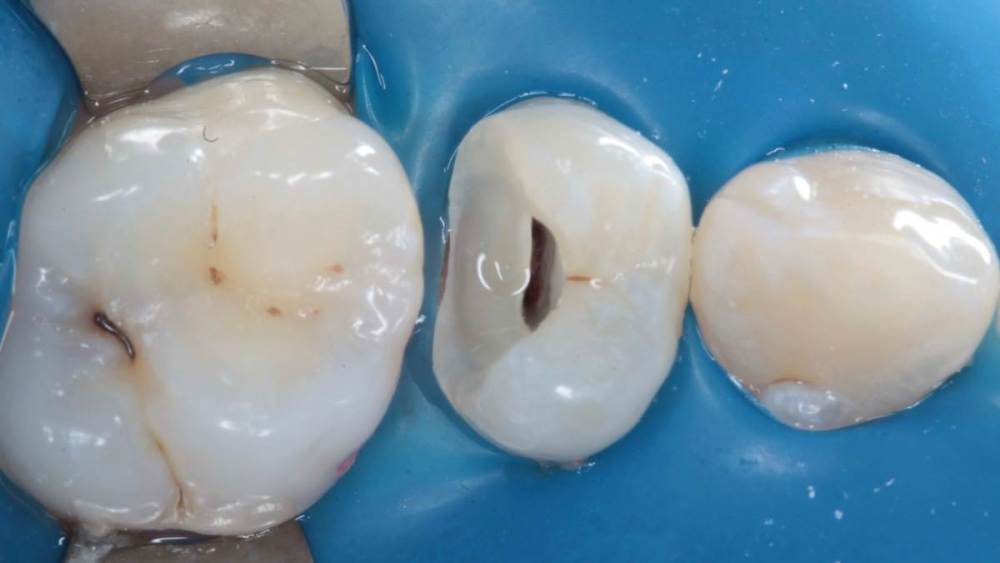

Гарриевич Опубликовано 21 мая, 2022 Поделиться Опубликовано 21 мая, 2022 (изменено) Будущее за регенеративной эндодонтией?) лечение в 2 посещения из-за нехватки времени (новый ассистент, перегруз пациентами, мысли о поднятии стоимости лечения, гипердиагностика?) глубокая пульпотомия, триоксидент, композит. фото подробно выложил это снимок с временной пломбой мало ли что вы подумаете Изменено 21 мая, 2022 пользователем Гарриевич 1 Ссылка на комментарий

ЛанаМ Опубликовано 23 мая, 2022 Поделиться Опубликовано 23 мая, 2022 Показаниями к пульпотомии является острый очаговый пульпит, а судя по снимку там хронический пульпит + хронический фиброзный периодонтит. Я бы выбрала пульпэктомию. 1 1 Ссылка на комментарий

Гарриевич Опубликовано 23 мая, 2022 Автор Поделиться Опубликовано 23 мая, 2022 13 часов назад, ЛанаМ сказал: Показаниями к пульпотомии является острый очаговый пульпит, а судя по снимку там хронический пульпит + хронический фиброзный периодонтит. Я бы выбрала пульпэктомию. Спасибо за мнение, но Зуб адекватно реагировал на холодовой раздражитель Скрытия произошло в момент препарирования полости Ссылка на комментарий